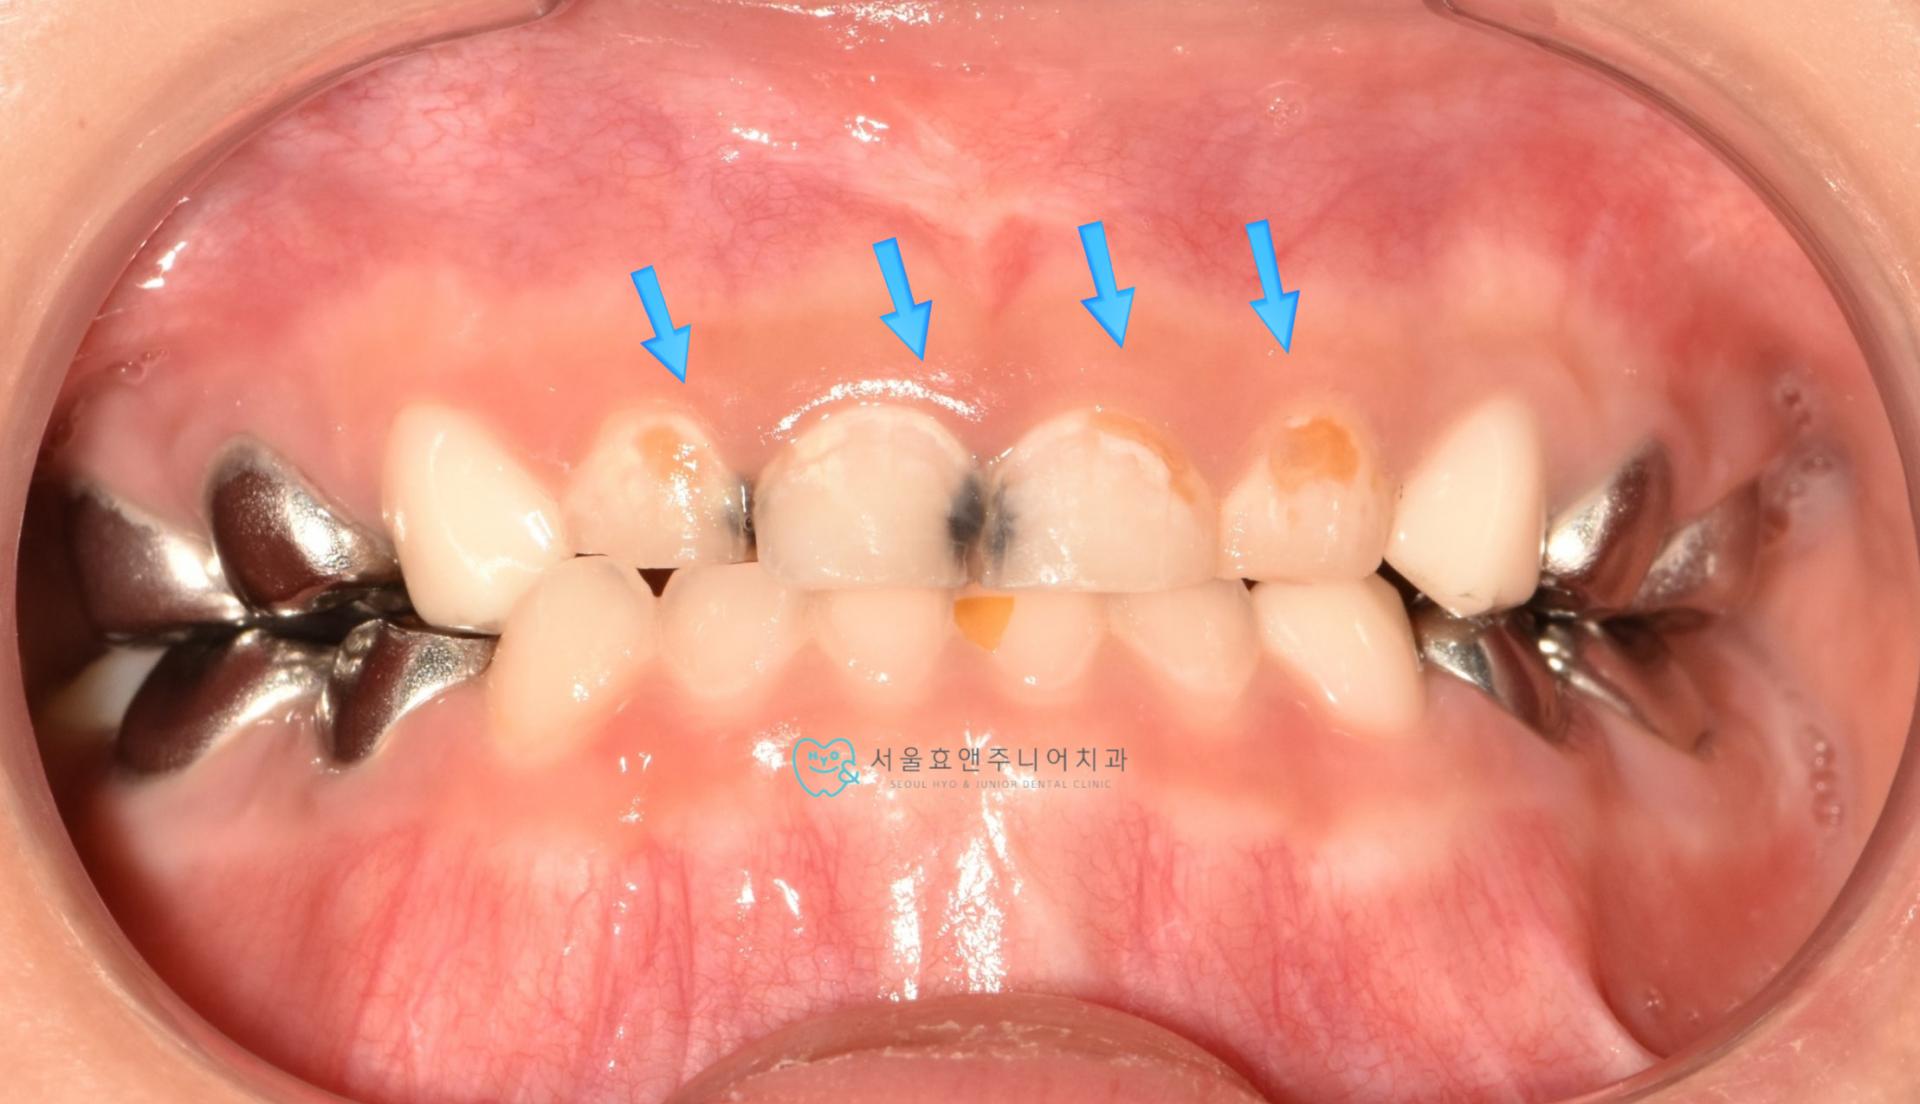

우리 친구는 만5세 친구로 앞니가 까맣게 썩어 보기 싫어 치료하고 싶다고 내원하셨습니다.

치료전 사진입니다.

아이유치앞니충치, 치료전사진입니다. 치아사이에 까맣게 충치가 보이네요.